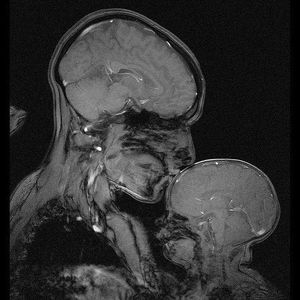

When MRI captures the love between a mother and a child! An image acquired by Rebecca Saxe and Atsushi Takahashi at the Massachusetts Institute of Technology (MIT).